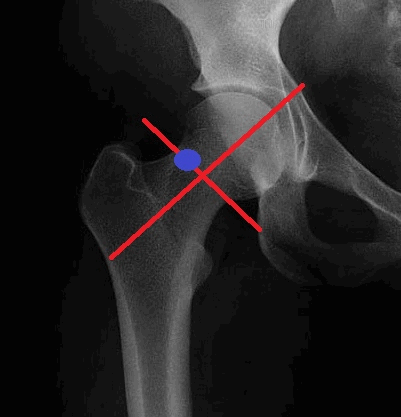

о Латеральный центрально-краевой угол Виберга: угол между вертикальной линией, проведенной через центр головки бедренной кости, и линией, проходящей через центр головки к латеральному краю вертлужной впадины:

- - 20-25°=пограничная дисплазия

- >40° = избыточное покрытие головки бедренной кости (предрасполагает к развитию импинджмента)

о Отсутствует покрытие >25% латерального или переднего края головки бедренной кости

Под контролем флюороскопа рисуется виртуальная линия разделяющая головку и шейку бедра и другая линия перпендикулярно заданной. Несколько выше точки их пересечения маркируется отметка.